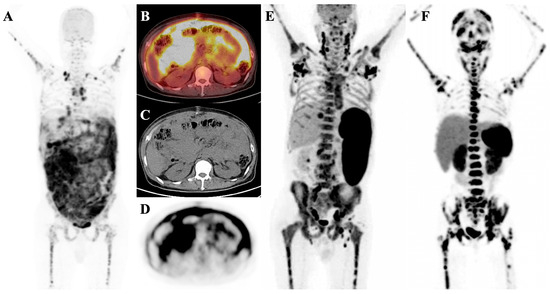

7.2. Metabolic Superscan